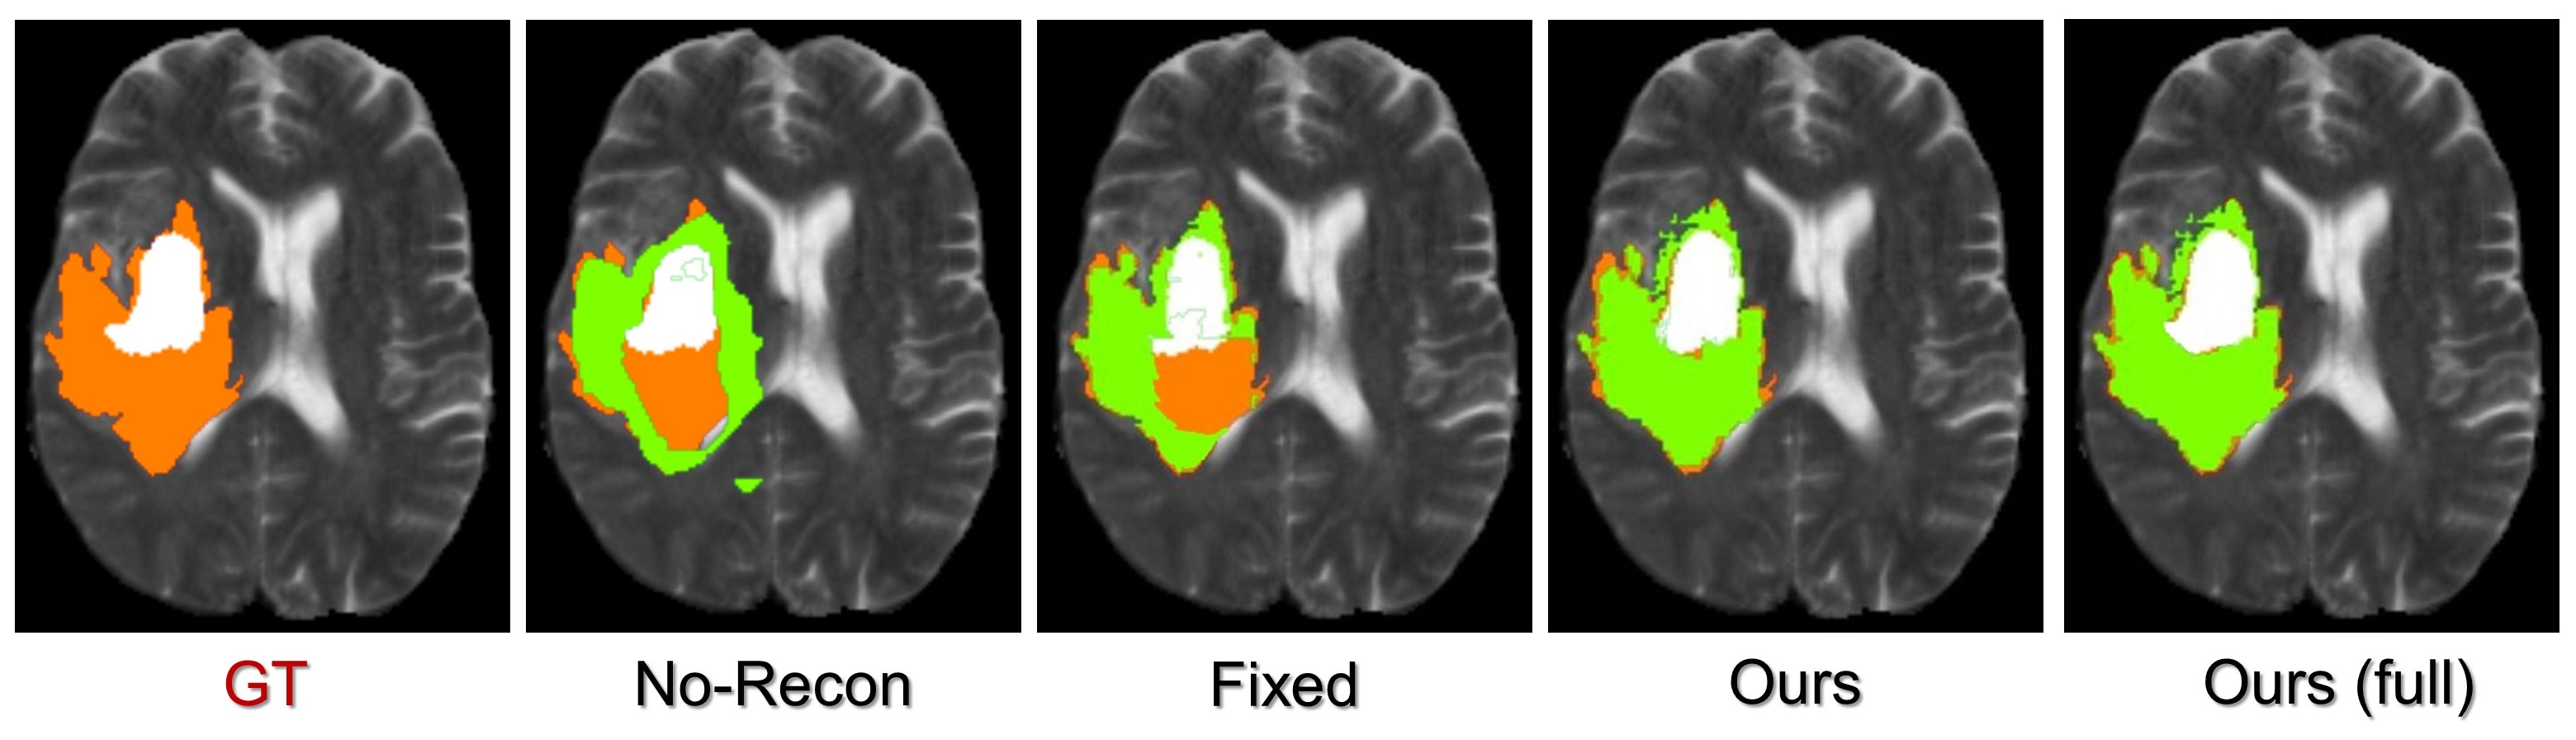

More comparison results can be found in the supplementary document of this paper. We also show its clinical value for segmentation task on BraTS2020 [48].

Appendix C Segmentation on undersampled MRI

To further assess the clinical value of the proposed method, we apply it to the tumor segmentation task on undersampled MRI from the BraTS2020 [48] datatset. Here, the MRI is accelerated for 8-fold using radial trajectory. As illustrated in Fig. 11, the segmentation model will collapse when directly training from the undersampled MRI (No-Recon). Using the proposed method, we can get a similar performance when compared to the model based on the fully sampled data. Our method is much more efficient as we accelerate it for eight times.